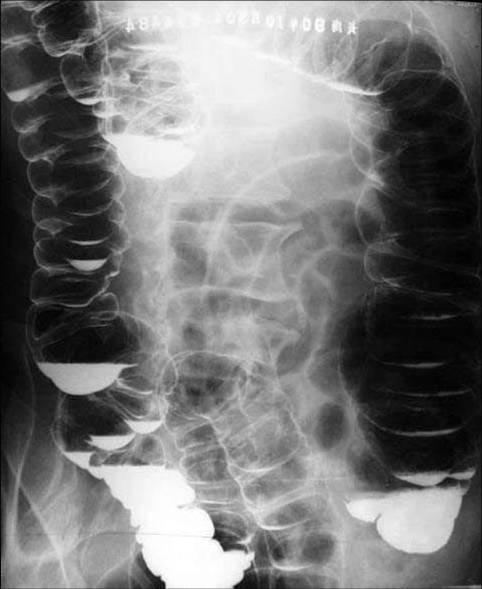

盲袢综合征(blind loop syndrome)是指小肠内容物在肠腔内停滞和细菌过度繁殖引起的腹泻、贫血、吸收不良和体重减轻的综合征。有人认为称之为小肠污染综合征(contaminated small bowel syndrome)似更确切。